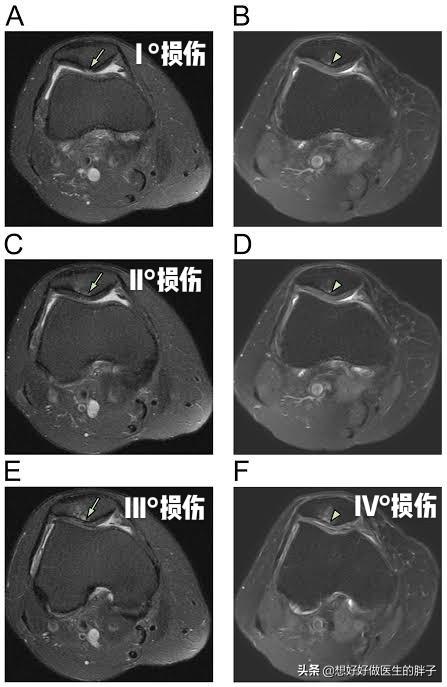

另外髌骨软骨软化比较经典的症状就是打软腿了。在走路的时候并没有什么特殊的诱因,膝盖会突然软一下,仿佛失去了对膝盖的控制一样。这个时候往往并不伴有疼痛,所以也很少有人在意,但是当症状越来越重,出现疼痛的时候再进行治疗可能就错过了治疗的最佳时机了!下图就是髌骨软骨不同程度软化的关节镜下影像学资料,看完之后,大家可能会对这个问题有一个更深的了解吧。

明确关节腔是否有软骨软化,主要靠医生的查体、患者的症状,另外需要进行膝关节核磁检查,因为软骨在x线下是不显影的,只有核磁才能看到关节腔内软骨的具体情况。